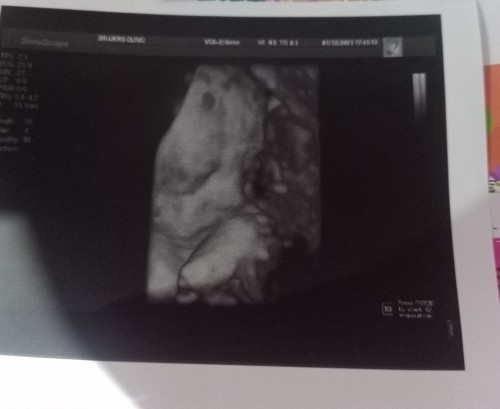

31week+3ค่ะ เพศชายค่ะ น้ำหนักน้อง1700กรัมไม่แน่ใจว่า ตามเกณฑ์หรือป่าว